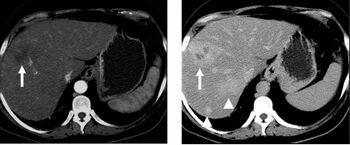

When evaluating hepatic masses, it can be advantageous to have both late arterial and portal venous phase images (biphasic imaging, figure 4) since some tumors enhance briskly during the arterial phase (hepatocellular carcinoma, hepatic adenoma, follicular nodular hyperplasia (FNH), and hypervascular metastasis), but may be occult or difficult to characterize on portal venous phase imaging alone (figure 6). However, it should be stressed that the addition of late arterial phase images is only indicated if one of these tumors is suspected, or if there is a need for further characterization of a hepatic mass, since the large majority of patients will not benefit from the addition of this phase. In addition, if there is a need to definitively characterize a hepatic mass, MRI is generally more sensitive and specific, with no associated radiation dose.[citation needed]

Transient hepatic attenuation differences in the arterial phase may mimic diseases of the liver.